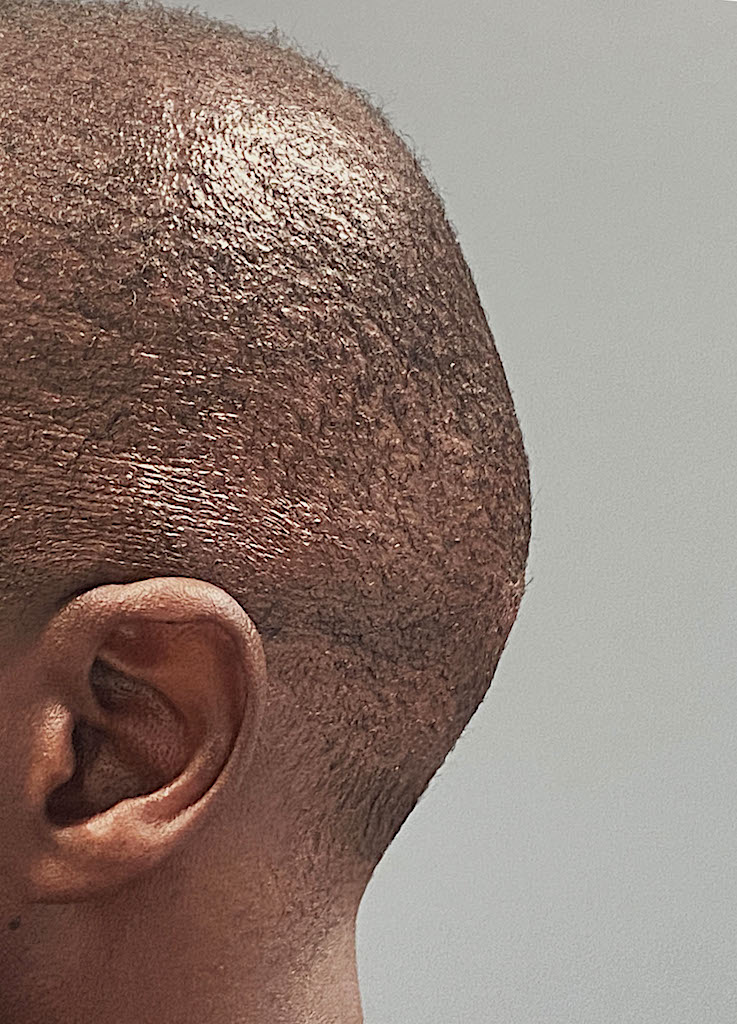

Desire for reshaping of an asymmetric flat back of the head in a shaved head male.

A combined back of the head reshaping procedure was done with a custom skull implant, sagittal ridge reduction and a right temporal muscle reduction.

Desire for reshaping of an asymmetric flat back of the head in a shaved head male.

A combined back of the head reshaping procedure was done with a custom skull implant, sagittal ridge reduction and a right temporal muscle reduction.